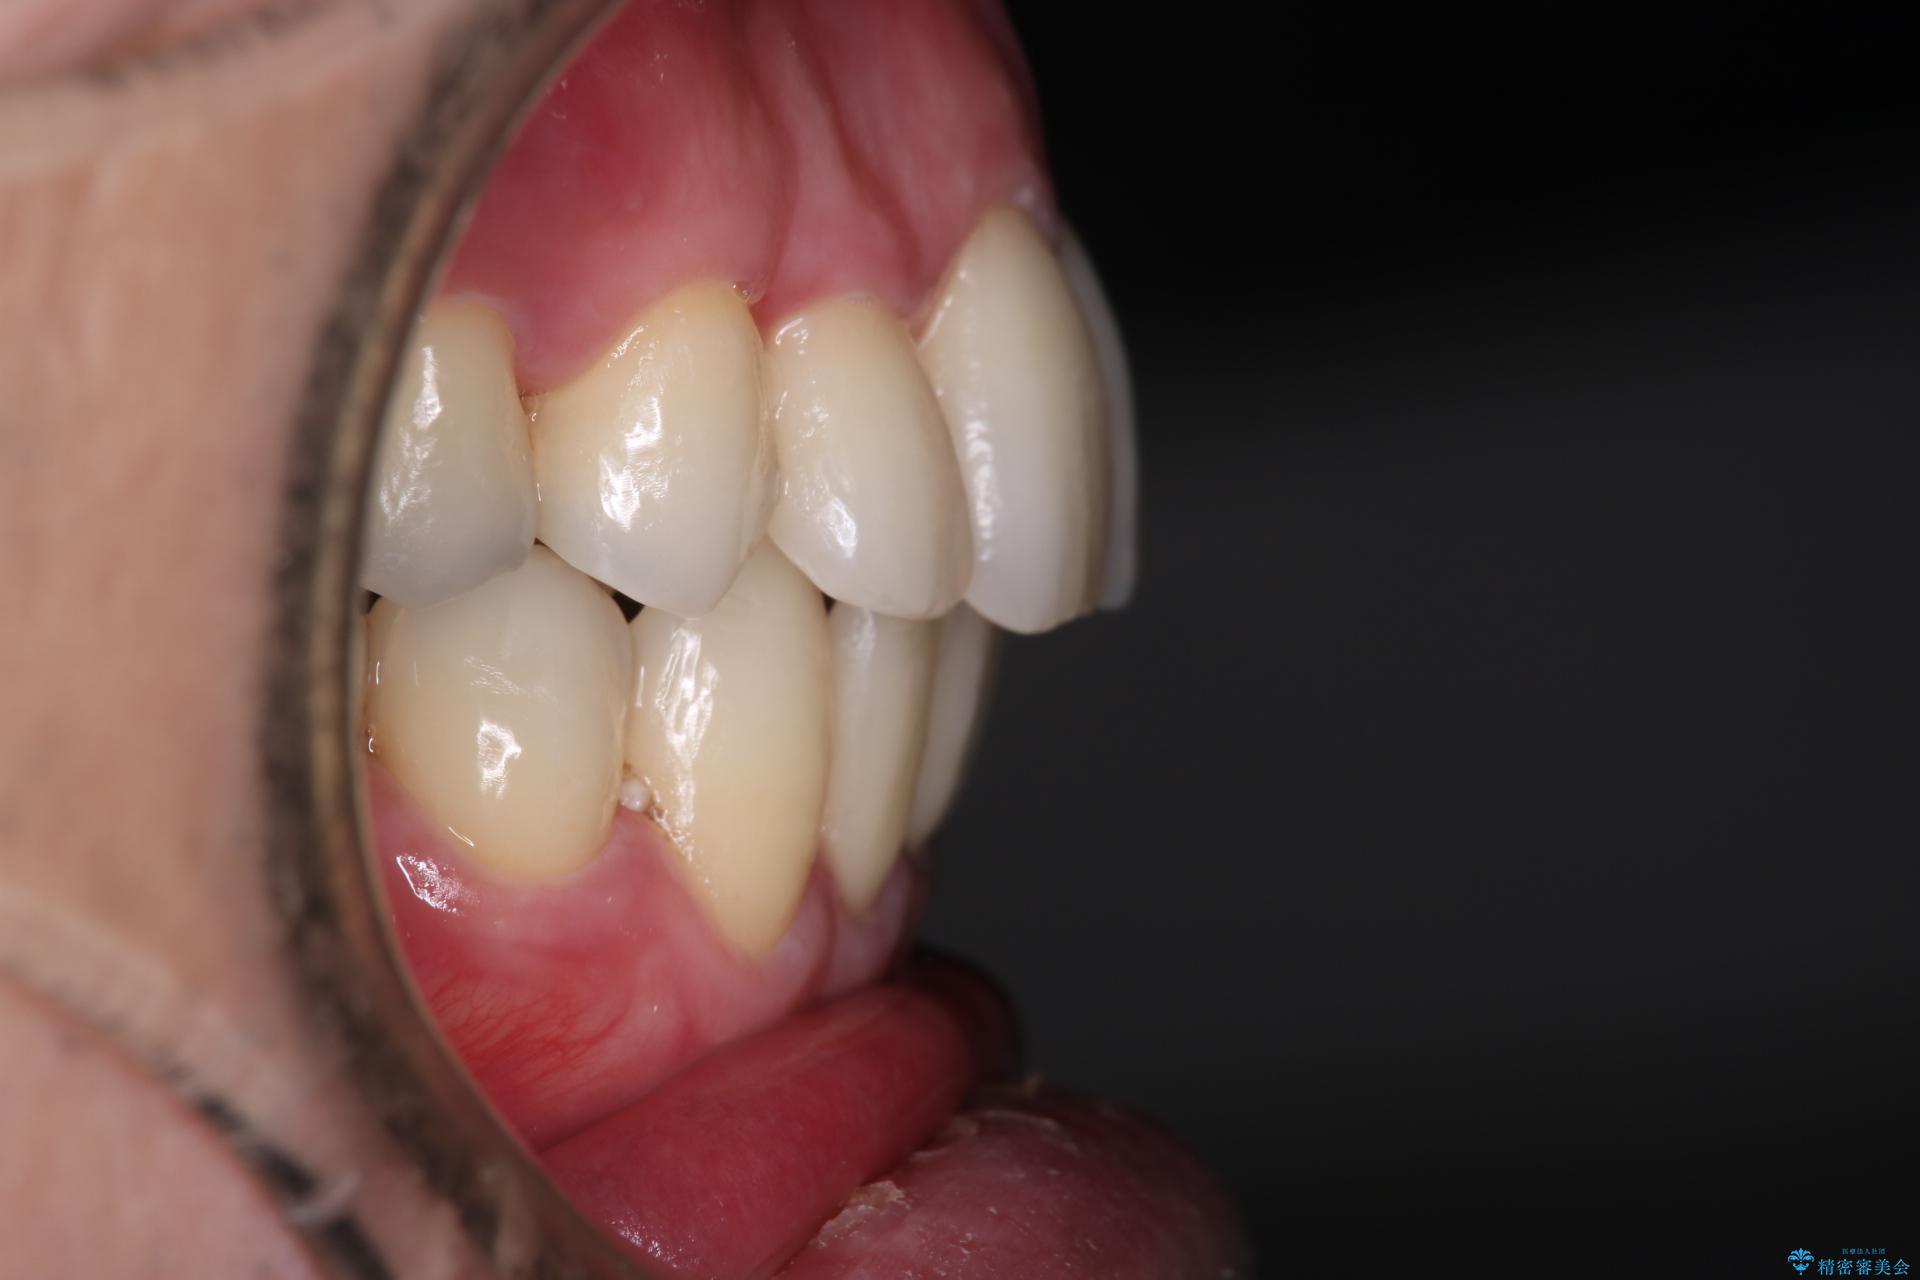

抜歯の本数を最小限に抑えたことで、治療計画も1年5ヶ月と短期間で終了することができ

主訴である前歯のがたつきも改善され綺麗な歯並びになりました。

矯正の装置を除去したタイミングで、ホワイトニングも行うことで歯の色味も白くなりました。